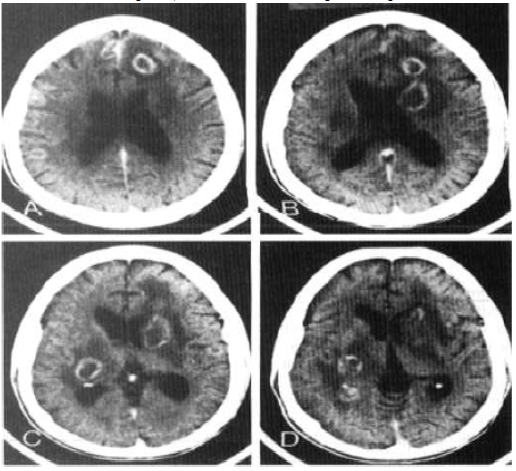

Sr. FS, 39 anos, convive com HIV há 10 anos, faz uso irregular de terapia antirretroviral e não sabe referir seu último

CD4 dosado. Ele procura atendimento no pronto-socorro por quadro de rebaixamento do nível de consciência há três

dias, associado à intensa cefaleia. Apresentou três episódios de convulsões tônico-clônicas generalizadas. O exame

neurológico simplificado demonstrou hemiparesia à esquerda, Glasgow 13, sem sinais de irritação meníngea e com

fundo de olho normal. Foi realizada tomografia, de acordo com a imagem a seguir:

Considere que a principal hipótese diagnóstica foi confirmada. Qual deve ser a conduta CORRETA?